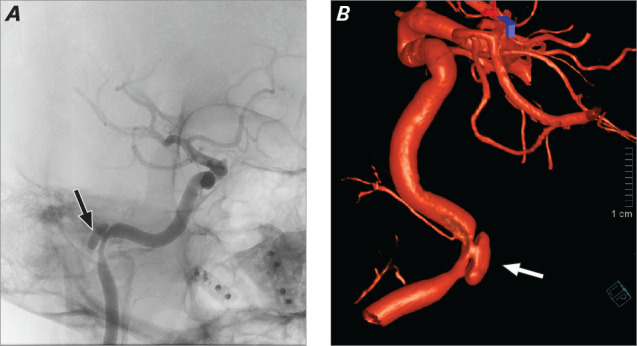

自发性颈动脉夹层是颈内动脉或椎动脉壁的非创伤性撕裂,是中风的常见原因,尤其是在 40 岁以下的患者中;然而,颈内动脉石刻状夹层极为罕见。本病例报告描述了一名 50 岁女性自发性颈内动脉瓣内夹层,被认为是继发于活动性 SARS-CoV-2 感染;夹层通过分流支架得到了成功治疗。

Spontaneous cervical artery dissection, a nontraumatic tear in the wall of an internal carotid or vertebral artery, is a common cause of stroke, particularly in patients younger than 40 years of age; however, petrous internal carotid artery dissection is extremely rare. This case report describes a 50-year-old woman who had a spontaneous intrapetrous internal carotid dissection thought to be secondary to active SARS-CoV-2 infection; the dissection was treated successfully with a flow-diverter stent.